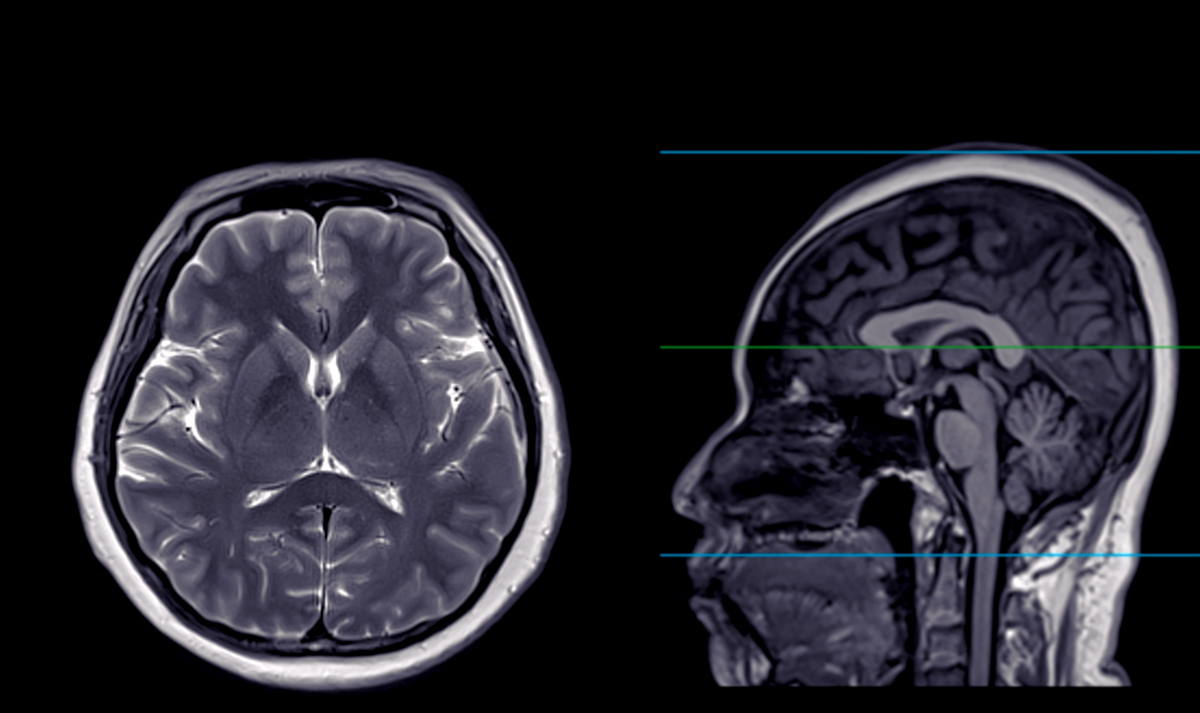

脑疝是指颅内压力增高导致颅内结构向颅腔内移位的一种严重的疾病。脑疝可分为以下几种类型:

2. 中线脑疝:颅内压力增高导致大脑中线结构向对侧移位,常见的有小脑扁桃体疝、大脑矢状窦疝等。症状包括昏迷、瞳孔异常、脑神经损害等。

3. 小脑幕下脑疝:颅内压力增高导致小脑幕下结构向颅腔内移位,压迫脑干。症状包括眼球运动障碍、共济失调、昏迷等。